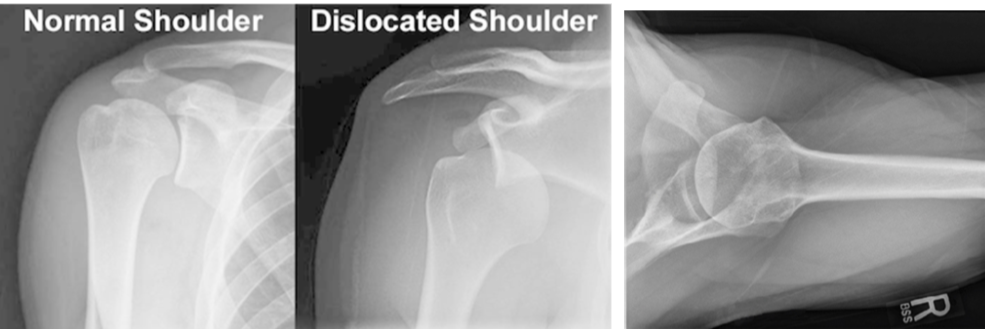

Shoulder Dislocation Imaging

Where is the ball in relation to the socket?

A

Ball in front of socket

• ______ view is mandatory in order to rule out a ______ dislocation

• Always need to study x-rays to rule out an associated proximal _______ fracture. (stat __ if unsure _______ reduction)

• Axillary view is mandatory in order to rule out a posterior dislocation

• Always need to study x-rays to rule out an associated proximal humerus fracture. (stat CT if unsure BEFORE reduction)

• axial view = beam is directed into axilla from below